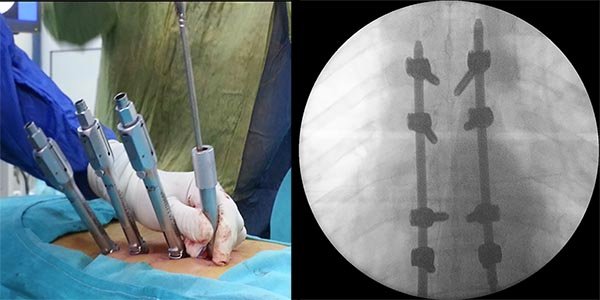

Figura 5:

Caso 8. Se realizó una estabilización percutánea T6-T10. El paciente retornó a UTI, para estabilizar su cuadro respiratorio y hemodinámico.

Figura 7:

Caso 8. Control postoperatorio alejado del paciente con un buen callo de fusión, sin pérdida de corrección.